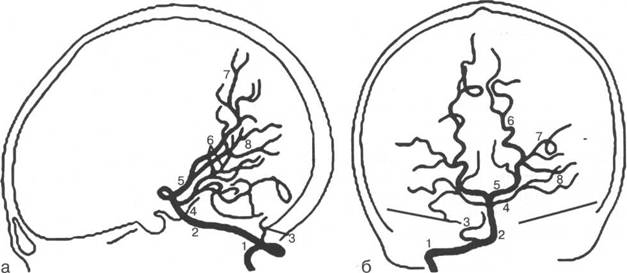

1 - сифон внутренней сонной артерии; 2 - глазничная артерия; 3 - восходящая часть передней мозговой артерии (А2); 4 - дуга передней мозговой артерии вокруг колена мозолистого тела (A3); 5 - перикаллезная артерия; 6 - лобно-полюсная артерия; 7 - каллезо-маргинальная артерия; (Ml);